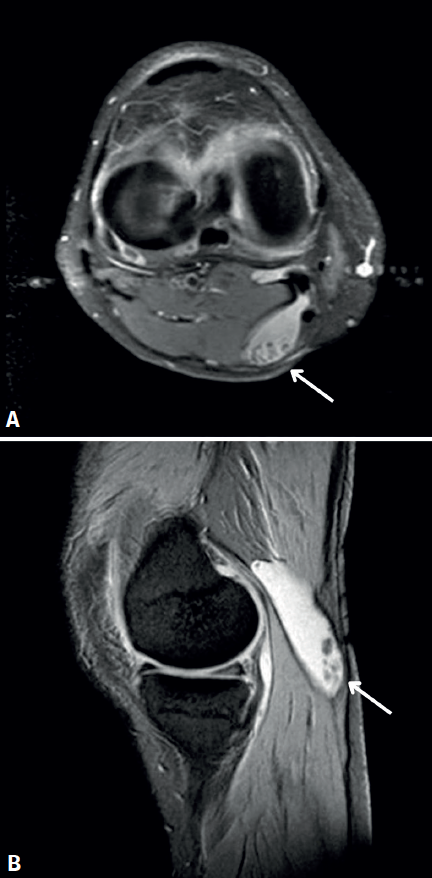

La radiografía no mostró hallazgos significativos. La resonancia magnética (RM) reveló una rotura degenerativa del menisco medial y un quiste de Baker posteromedial, con pequeñas tumoraciones redondeadas de densidad cartilaginosa dentro de este (Figura 1).